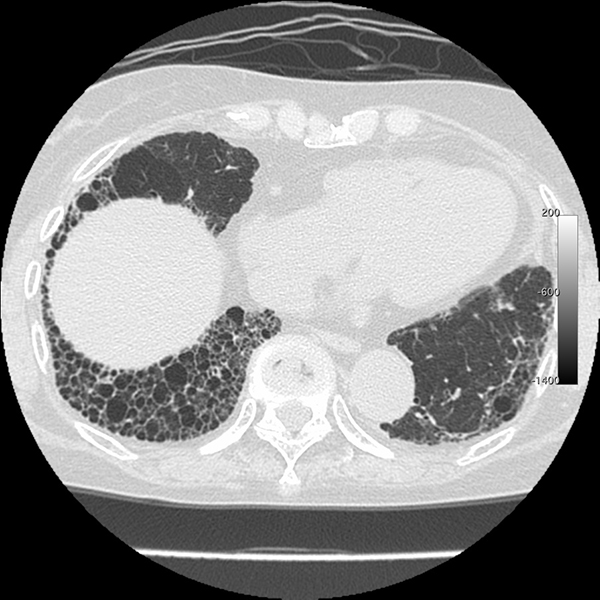

症例033 サイトメガロウイルス肺炎 Mediflex Incorporated